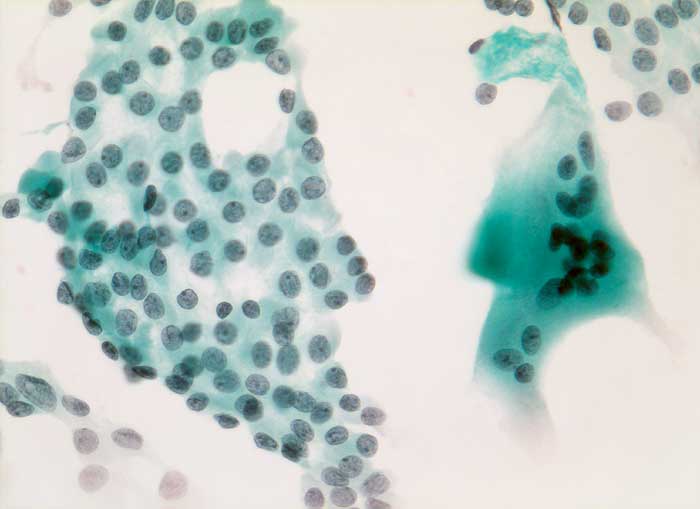

Die zytologischen Ausstriche sind meist zellreich und enthalten grosse einschichtige Zelltapeten in regelmässiger honigwabenartiger Anordnung. Dreidimensionale verzweigte Papillen mit fibrovaskulären Stromastielen finden sich lediglich in 10-60% der Fälle. Follikuläre Strukturen sind in bis zu 85% der Fälle zu sehen. Der Hintergrund ist oft zystisch mit Schaumzellen und mehrkernigen Riesenzellen. Gelegentlich lassen sich Psammomkörperchen nachweisen. Sehr wichtig für die Diagnose sind folgende Kernkriterien: leicht vergrösserte uniforme Kerne, unregelmässige Kernmembran, Kernkerben (grooves), intranukleäre Zytoplasmainvaginationen und prominenter eosinophiler Nukleolus.

Die Abbildungen zeigen zwei verschiedene Fälle eines papillären Schilddrüsenkarzinoms.